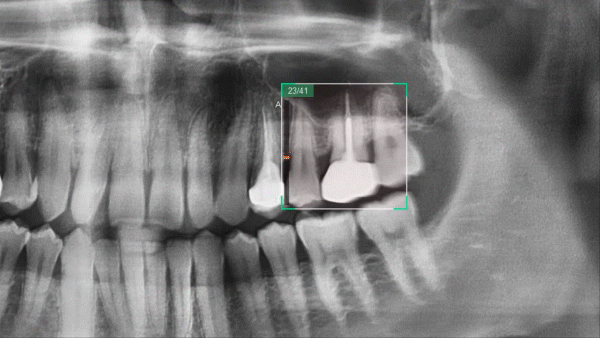

Insight 2.0

Функция Insight Pan предназначена для создания многослойных панорамных изображений, позволяющих детально исследовать анатомические структуры на различных глубинах. В версии Insight 2.0 эта функция была усовершенствована и получила обновленную возможность свободного выбора области обзора (FOV), что позволяет фокусироваться только на интересующих участках.